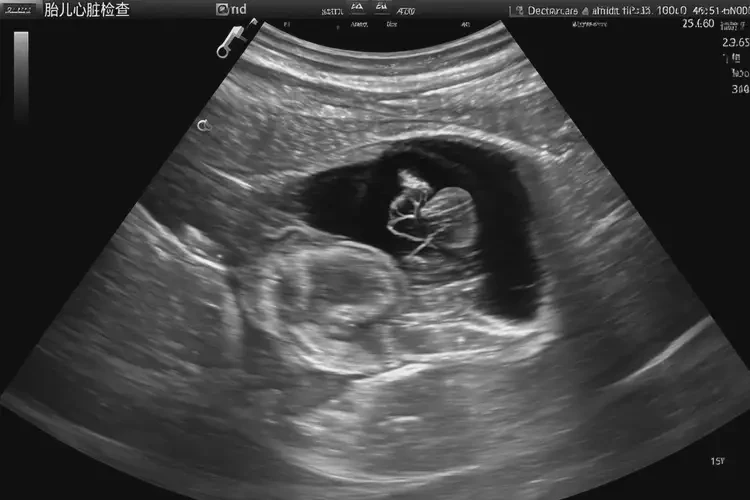

孕13周2天胎心70多還能保住嗎(圖1)